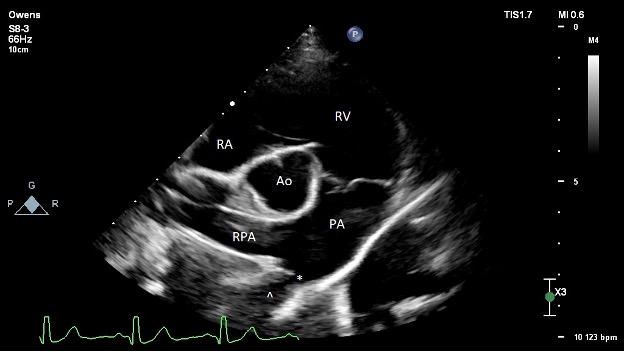

Pre-operative echocardiography (Figure 2):

The left ventricle is moderately dilated at end-diastole and severely dilated at end-systole. Normal fractional shortening and ejection fraction. Normal diastolic assessment. Normal estimated filling pressures.

The left atrium is moderately enlarged.

The right ventricle is normal in size and function.

The right atrium is normal in size.

The aortic valve is structurally normal with no subvalvular ridge of tissue and trace AI. The LVOT velocity is mildly elevated (2.2 m/s). This is thought secondary to the increased stroke volume secondary to the left-to-right shunt given the normal valve appearance.

The mitral valve structure appears normal. There is trace to mild central mitral regurgitation due to annular dilation. Unable to interrogate with spectral Doppler.

The tricuspid valve appears normal. There is trace tricuspid regurgitation.

The pulmonic valve is normal. The RVOT velocity is normal. The PA is dilated due to the continuous high velocity L-R flow.

There is no pericardial effusion.

There is a moderately sized L-to-R shunting patent ductus arteriosus (PDA) present. Minimal ductal diameter measures around 3.5-4.2 mm. There is a dilated ampulla with relatively acute tapering at the pulmonary insertion site, consistent with a Miller type 2 ductal morphology (A vs. B unable to classify on TTE). Normal transductal velocity (5.1 m/s) without evidence of significantly elevated PA pressures. No other congenital defects present.

PICTURE: Figure 2: Pre-operative transthoracic echocardiography image obtained from the right parasternal short axis at the level of the heart base. The ostium of the PDA is denoted with an asterisk (*). The ampulla of the ductus is denoted with a caret (^). RA = right atrium; RV = right ventricle; PA = main pulmonary artery; RPA = right pulmonary artery; Ao = aorta